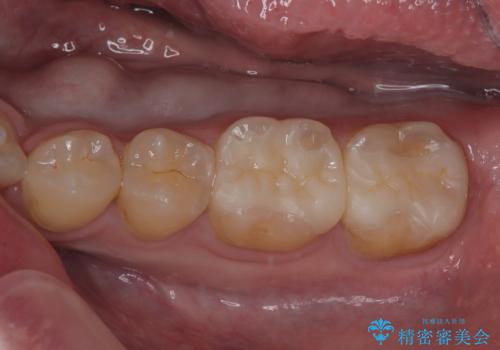

銀歯を外したい オールセラミッククラウン

担当医 有澤哲郎